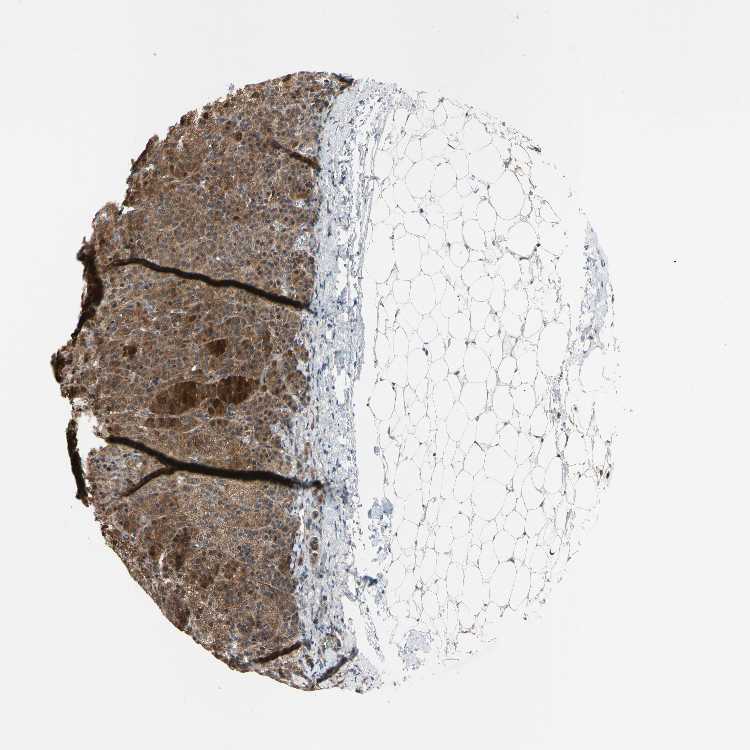

TISSUE PRIMARY DATA ADRENAL GLAND Show tissue menu

ADRENAL GLAND - Antibody stainingi

Antibody staining in the annotated cell types in the current human tissue is reported as not detected, low, medium, or high, based on conventional immunohistochemistry profiling in selected tissues. This score is based on the combination of the staining intensity and fraction of stained cells.

Each image is clickable and will lead to virtual microscopy that enables deeper exploration of all samples and also displays staining intensity scores, fraction scores and subcellular localization as well as patient and tissue information for each sample.

Antibody HPA020095Antibody HPA020138Antibody CAB010878Antibody CAB080402

Glandular cells MediumMediumMediumLow